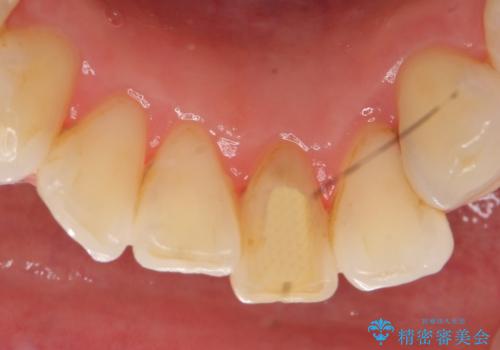

- 下顎前歯が茶色いのが気になるのでセラミックで治療したいといらっしゃった方の症例です。

再根管治療後、オールセラミッククラウン(スペシャル)による補綴を行いました。